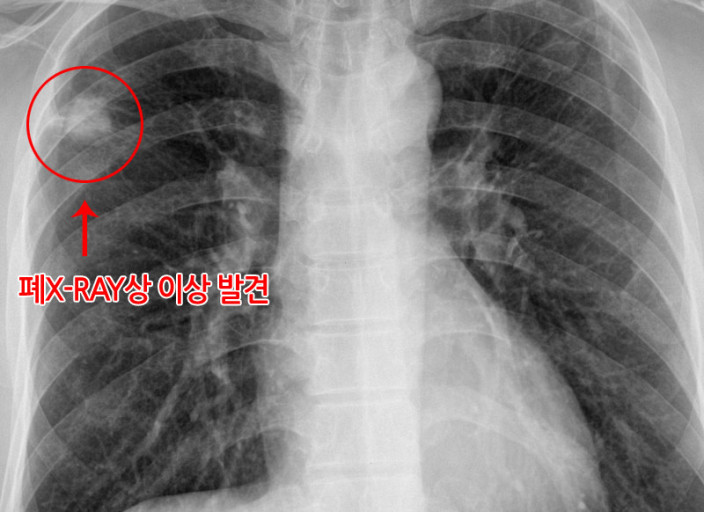

- 정기적인 건강 검진: 특히 흡연자나 가족력이 있는 경우, 저선량 흉부 CT와 같은 정밀 검진을 통해 조기에 발견해야 합니다.